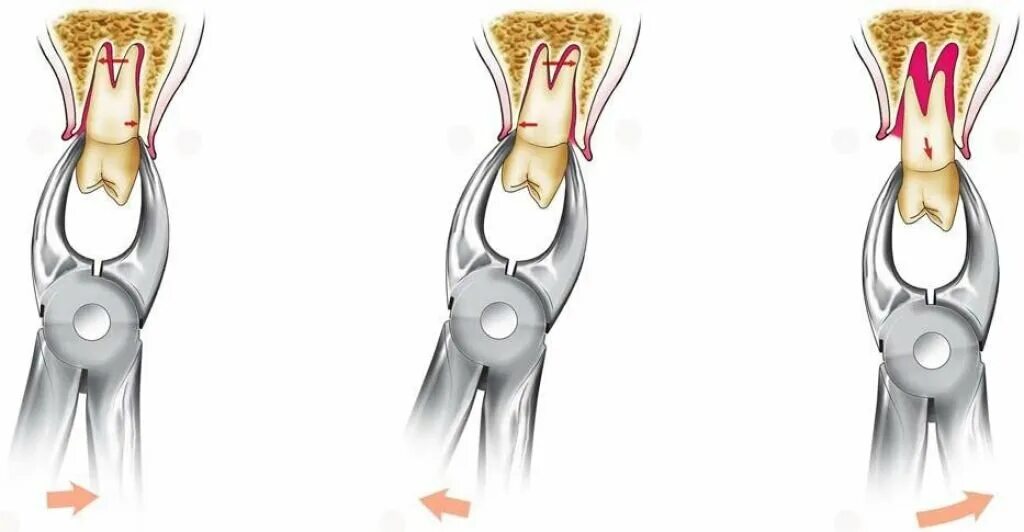

Удалить зубы семерки